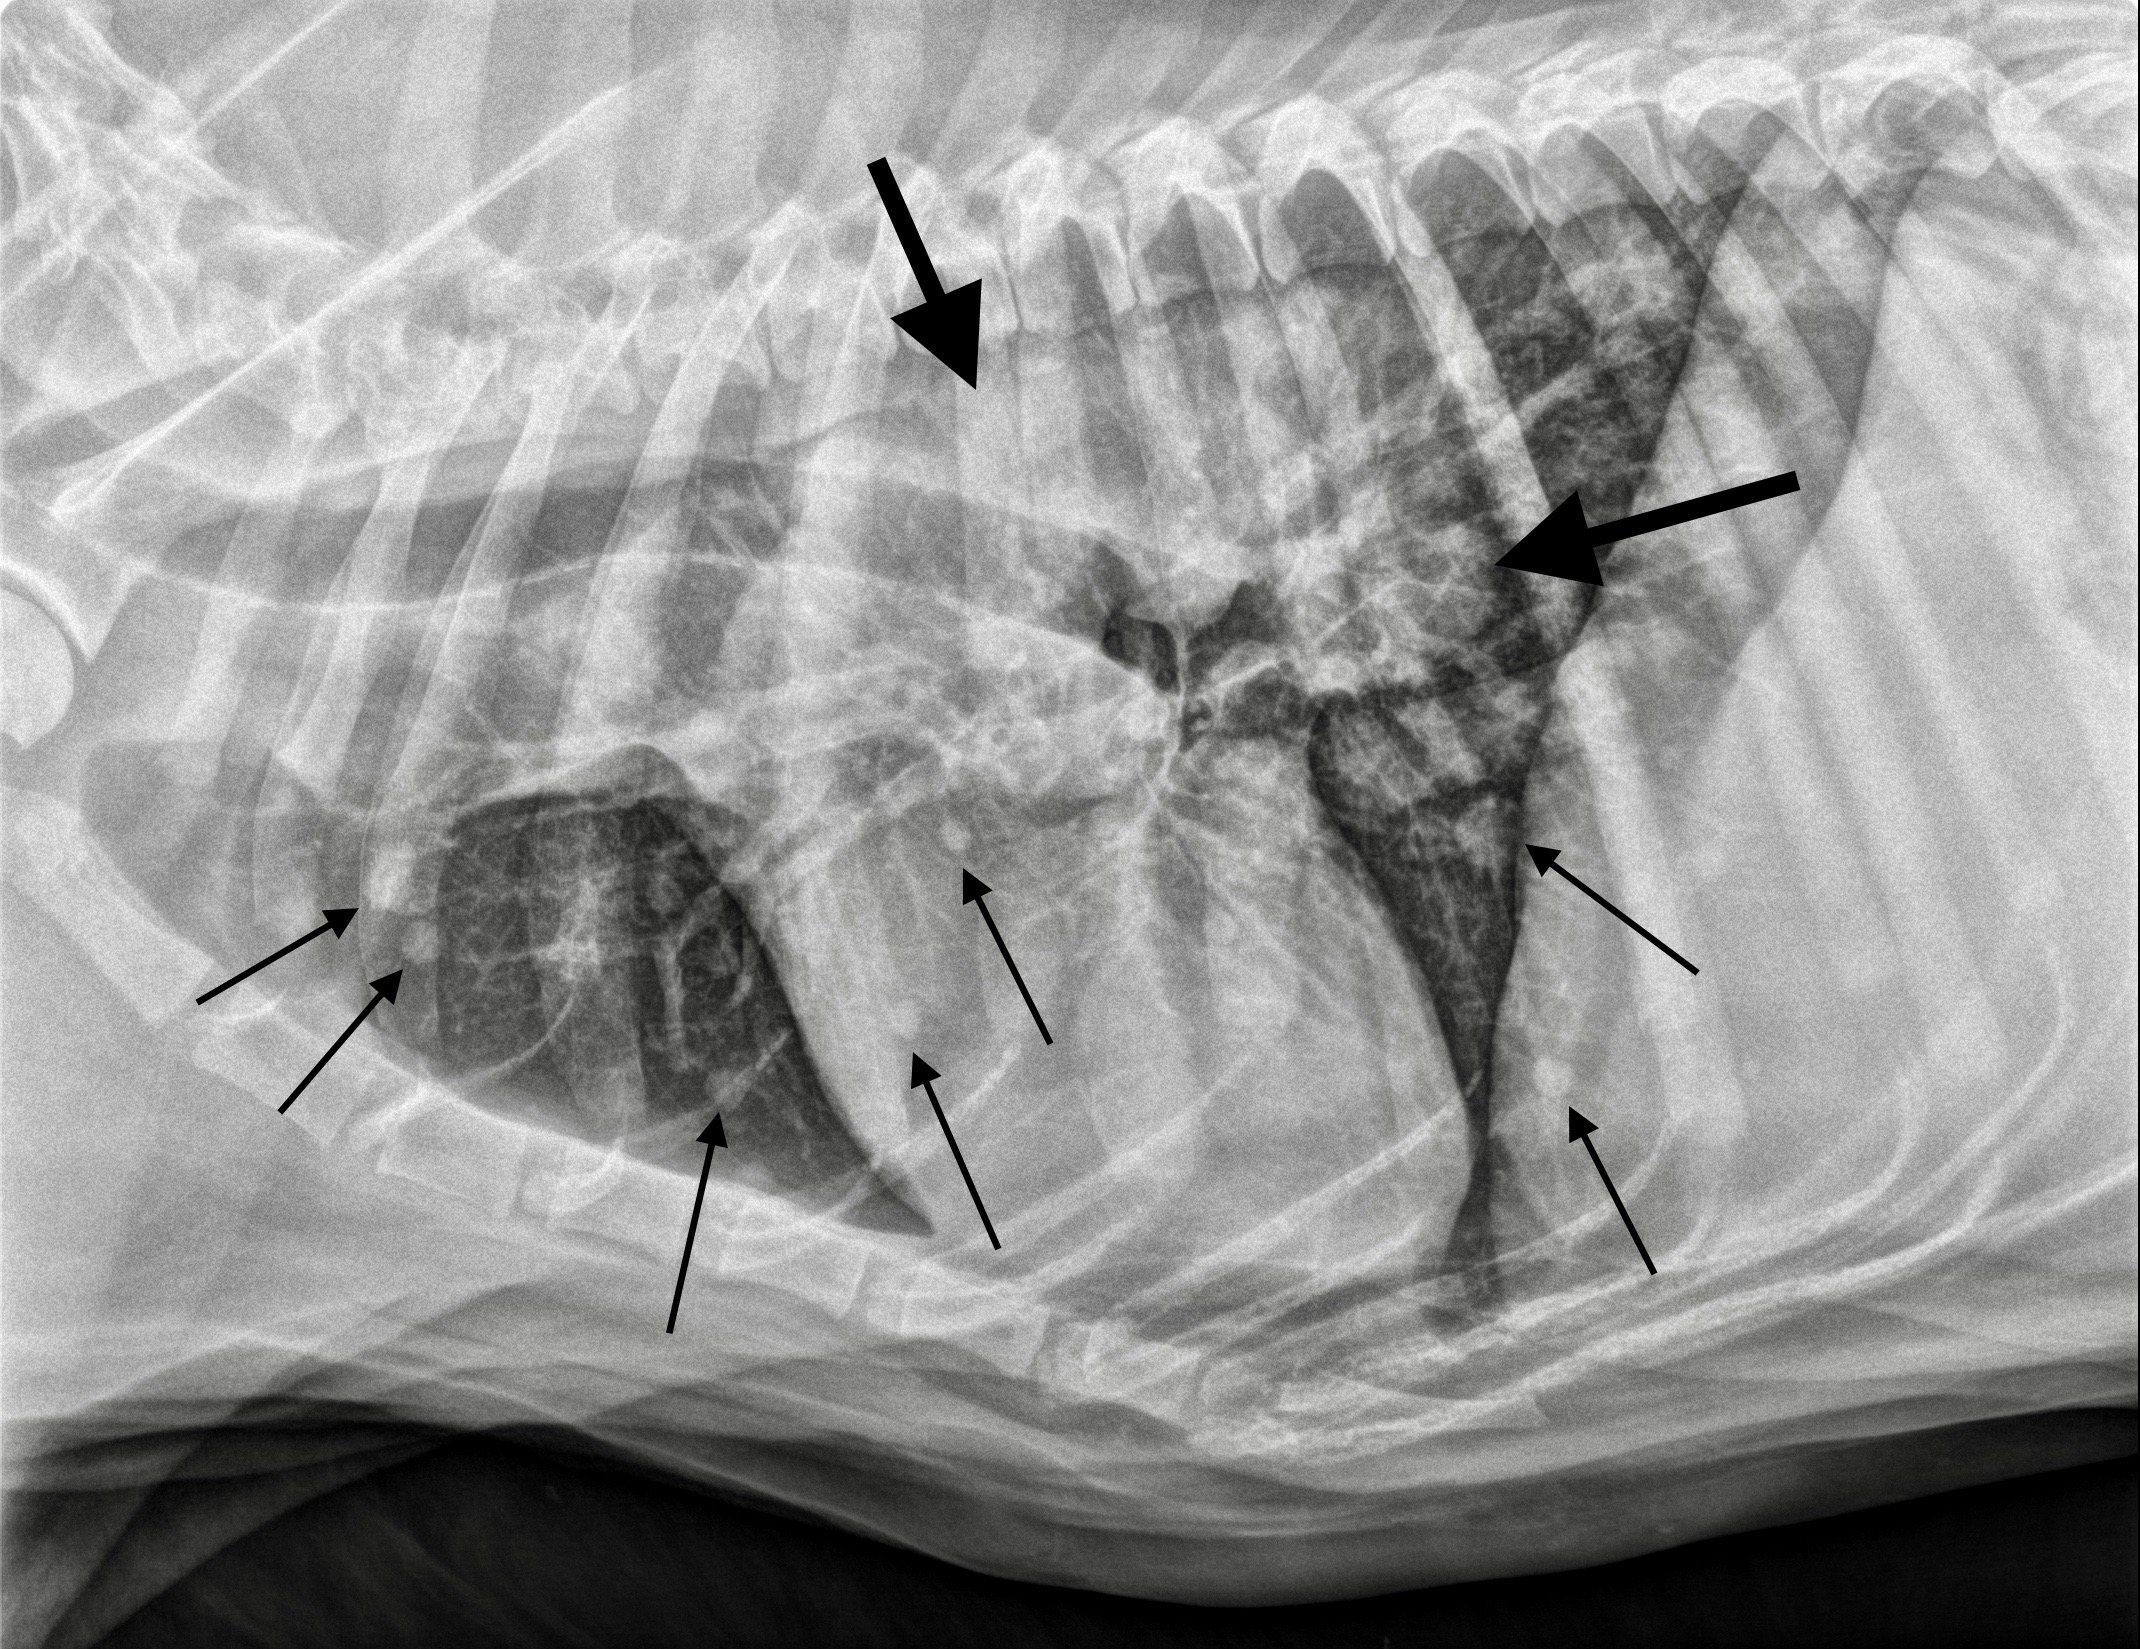

Multiples nodules dans la rate d’une chienne de race croisée âgée de 10 ans. L’analyse a montré qu’il s’agissait d’un sarcome histiocytaire.